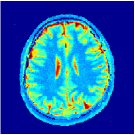

Two sets of experiments were conducted here: first, we used the 2D and 3D acquisition sequences for scanning a healthy volunteer’s brain (real-world acquisitions). Figures 6 and 7 display the parametric maps reconstructed from 2D spiral and radial readouts. We computed the T1, T2 and proton density (PD) maps using baseline reconstruction algorithms ZF, VS, LR, FLOR, AIR-MRF and our proposed LRTV. While baselines use DM either for quantitative inference or also during reconstruction (i.e. AIR-MRF), we further compare the DM-free LRTV’s performance when cascaded to DM, KM and MRFResnet for quantitative inference. For the 3D spiral acquisitions we compared LRTV and its closest competitor VS in Figure 8. Outcomes from other tested algorithm are displayed in the supplementary materials (Figure S5). Since FLOR does not use dimensionality-reduction, our system ran out of memory during 3D reconstruction; hence results are not reported in this case.

The LRTV-DM and LRTV-MRFResnet perform on par, and both outperform all tested baselines for reconstructing T1, T2 and PD maps in all acquisition schemes. This can be observed both visually in Figures 6, 7, 8, S2 and S3, and quantitatively in Table IV across all tested metrics. Other baselines were unable to successfully remove the under-sampling artefacts in TSMIs, and these errors propagated to the parameter inference phase and resulted in inaccurate maps. Temporal-only priors incorporated within LR are shown insufficient to regularise the inverse problem and LR sometimes (e.g. 2D spiral acquisitions) can admit solutions with even stronger artefacts than the model-free ZF baseline. This issue was previously studied for other non-Cartesian MRF readouts that similar to our spiral/radial trajectories, miss to sample the corners of the k-space in all timeframes (see section 2.2.2 and figure 2 in [19]). In the absence of reference for the k-space corners information, the LR iterations despite minimising the objective can converge to solutions with high-frequency artefacts, as visible in the computed maps. This highlights the need for adding an appropriate spatial-domain regularisation. FLOR reduces the LR’s artefacts but this improvement is limited because the suggested nuclear norm penalty does not incorporate an explicit spatial regularisation. Further for reducing artefacts, FLOR can introduce an undesirable bias in the computed T1/T2 maps e.g. see error maps in Figures S2 and S3. The non model-based VS baseline incorporates spatial regularisation and results in spatially smoother maps than ZF and LR, but it is unable to output artefact-free images. Further and consistent with our in-vitro experiment, we observe that VS overestimates the T2 values (e.g. in White and Grey matter regions) in tested 2D acquisitions i.e. the spatial regularisation trades off agains the quantification accuracy. The model-based AIR-MRF adds spatial regularisation through 2D/3D low-pass Gaussian filters however this trades off the sharpness of the computed maps and can increase the errors at the tissue boundaries (we searched Gaussian spreads that keep the blurs and high-frequency artefacts minimal). For our acquisition readouts, Gaussian filters performed better than disk filters of [19] for avoiding strong Gibbs artefacts. On the other hand, the spatiotemporally regularised LRTV greatly improves the TSMI reconstructions i.e. 4 dB enhancement compared to the closest competitor baseline (Table IV). This enables computing accurate and aliased-free multi-parametric inference using DM or the DM-free learning-based alternative MRFResnet as visible in Figures 6, 7, 8, S2 and S3. MRResnet and DM score competitive quantitative inference results i.e. T1 and T2 MAPE less than 5% and 9%, respectively (Table IV). KM also outputs comparably accurate T1 maps, however this shallow learning model despite having a model size larger than MRFResnet, is unable to learn accurate T2/PD quantification and it results in poor estimated maps, consistent with our observations in section VI-C.